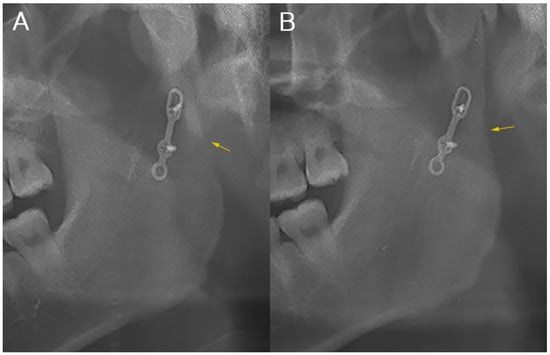

| Radio-density (Mean grayscale value of ROI) | Semi-rigid | 100.5 ± 17.4 | 102.5 ± 18.4 | 0.035 |

| Rigid | 120.7 ± 31.4 | 124.1 ± 28.7 | 0.044 | |

| p-Value | 0.041 | 0.013 | ||